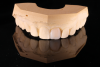

(33.) Retracted view with the teeth apart and close-up view of the definitive screw-retained zirconia restoration in position (Definitive restoration fabricated by Sam Alawie and Beverly Hills Dental Lab).

Figure 33

(34.) Retracted view with the teeth apart and close-up view of the definitive screw-retained zirconia restoration in position (Definitive restoration fabricated by Sam Alawie and Beverly Hills Dental Lab).

Figure 34